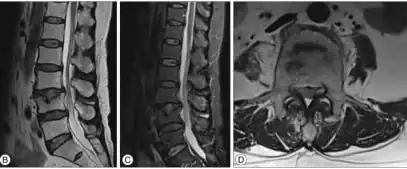

b,c,d) MRI present a minimal Schmorl's node at L4 -

Schmorl's nodes can be detected with X-rays, although they can be imaged better by CT or MRI. They are considered to be vertical disc herniations through the cartilaginous vertebral body endplates. Schmorl's nodes can sometimes be seen radiographically, however they are more often seen on MRI, even when not visible on plain X-rays. They may or may not be symptomatic, and their etiological significance for back pain is controversial. In a study in Spine by Hamanishi, et al., Schmorl's nodes were observed on MRI in 19% of 400 patients with back pain, and in only 9% of an asymptomatic control group. The authors concluded that Schmorl's nodes are areas of "vertical disc herniation" through areas of weakness in the endplate.[4]